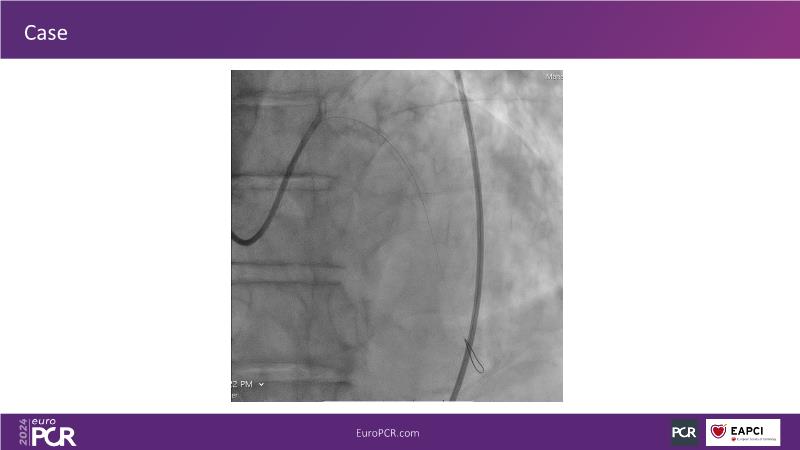

Tune into this 2024 session for insights into the latest ESC guidelines, strategies to prevent and treat no reflow, and an examination of trials like TASTE, TAPAS, and TOTAL on coronary thrombus management. Explore also the outcomes of the CHEETAH study, pondering a potential paradigm shift, and delve into a case study on thrombus removal in a patient with high thrombus burden.